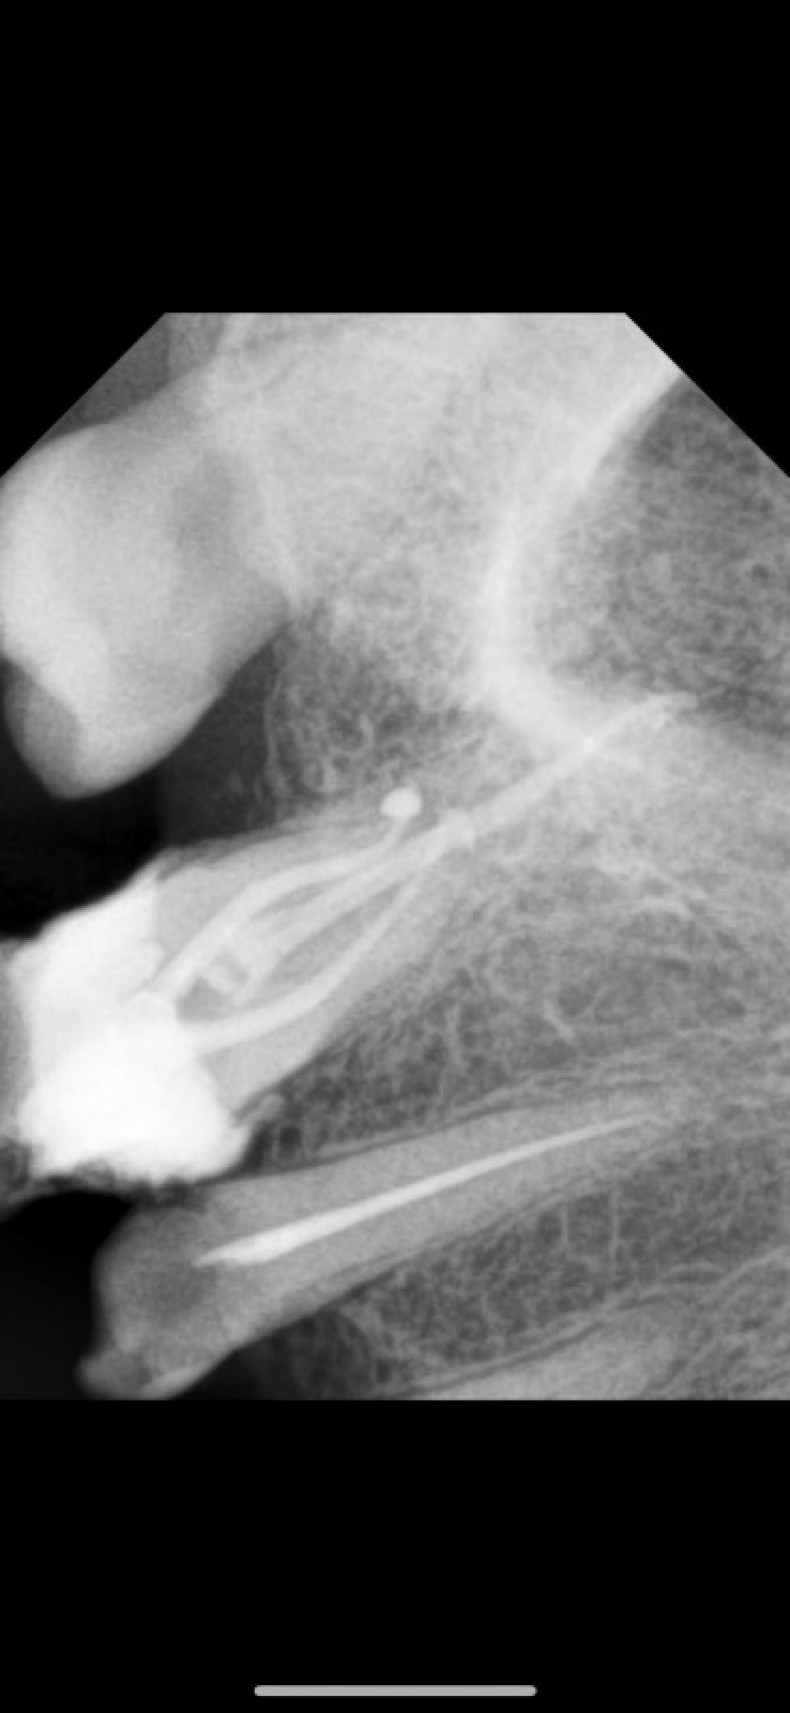

Лікування зубів під мікроскопом. Лікування карієсу, пульпіту, періодонтиту. Лікування захворювань ясен.

Лікування зубів під мікроскопом